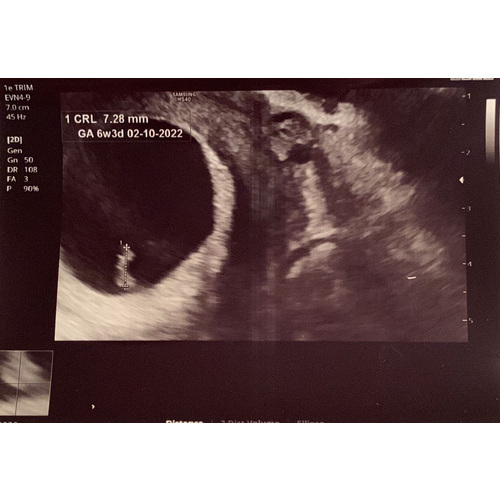

Maar hierbij een echo:

Het is heeel lastig.. Op het echobeeld 6w3d maar daarin zitten al de 2 gratis zwangerschapsweken ingerekend? Dan is het haast niet mogelijk om 8 januari een positieve test te hebben.

Maar op de echo zagen ze 6w3d. Zit in die echo niet de twee weken al ingerekend? Dus dan zou de echo een beeld laten zien van 4 weken oud vruchtje?